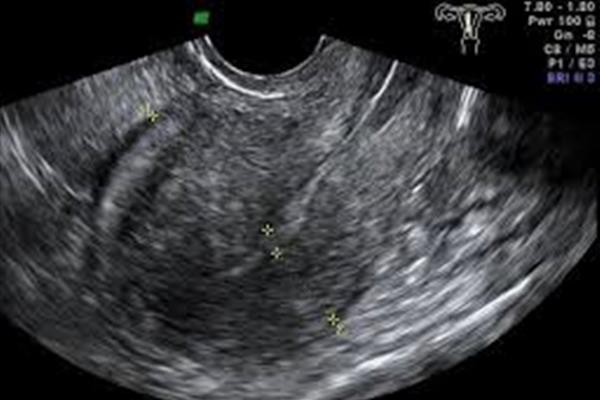

روشهای انجام سونوگرافی اوایل بارداری

سونوگرافی ترانسواژینال: این روش تصویری دقیقتر از رحم و جنین در هفتههای اولیه ارائه میدهد. برای این کار، پروب سونوگرافی درون واژن قرار میگیرد و به پزشک امکان میدهد که جزئیات بیشتری از رحم و جنین مشاهده کند.

اهمیت سونوگرافی اوایل بارداری

این سونوگرافیها از هفتههای ۴ تا ۶ بارداری، وضعیت جنین را از جنبههای مهمی چون تأیید بارداری، تشخیص خارج رحمی، تعیین سن دقیق بارداری، مشاهده تعداد جنینها و تشخیص ضربان قلب بررسی میکنند. این اطلاعات به پزشکان برای برنامهریزی دقیق بارداری و پایش سلامت جنین کمک میکند.

این سونوگرافیها، در هفتههای ۴ و ۵، حضور بارداری و مکان آن را تأیید میکنند. تشخیص به موقع بارداری خارج رحمی نیز از اهمیت خاصی برخوردار است.